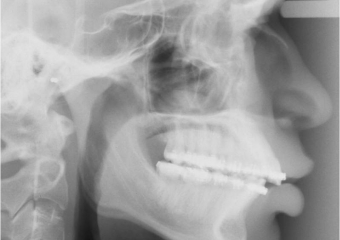

Raio x inicial

Raio x após cirurgia